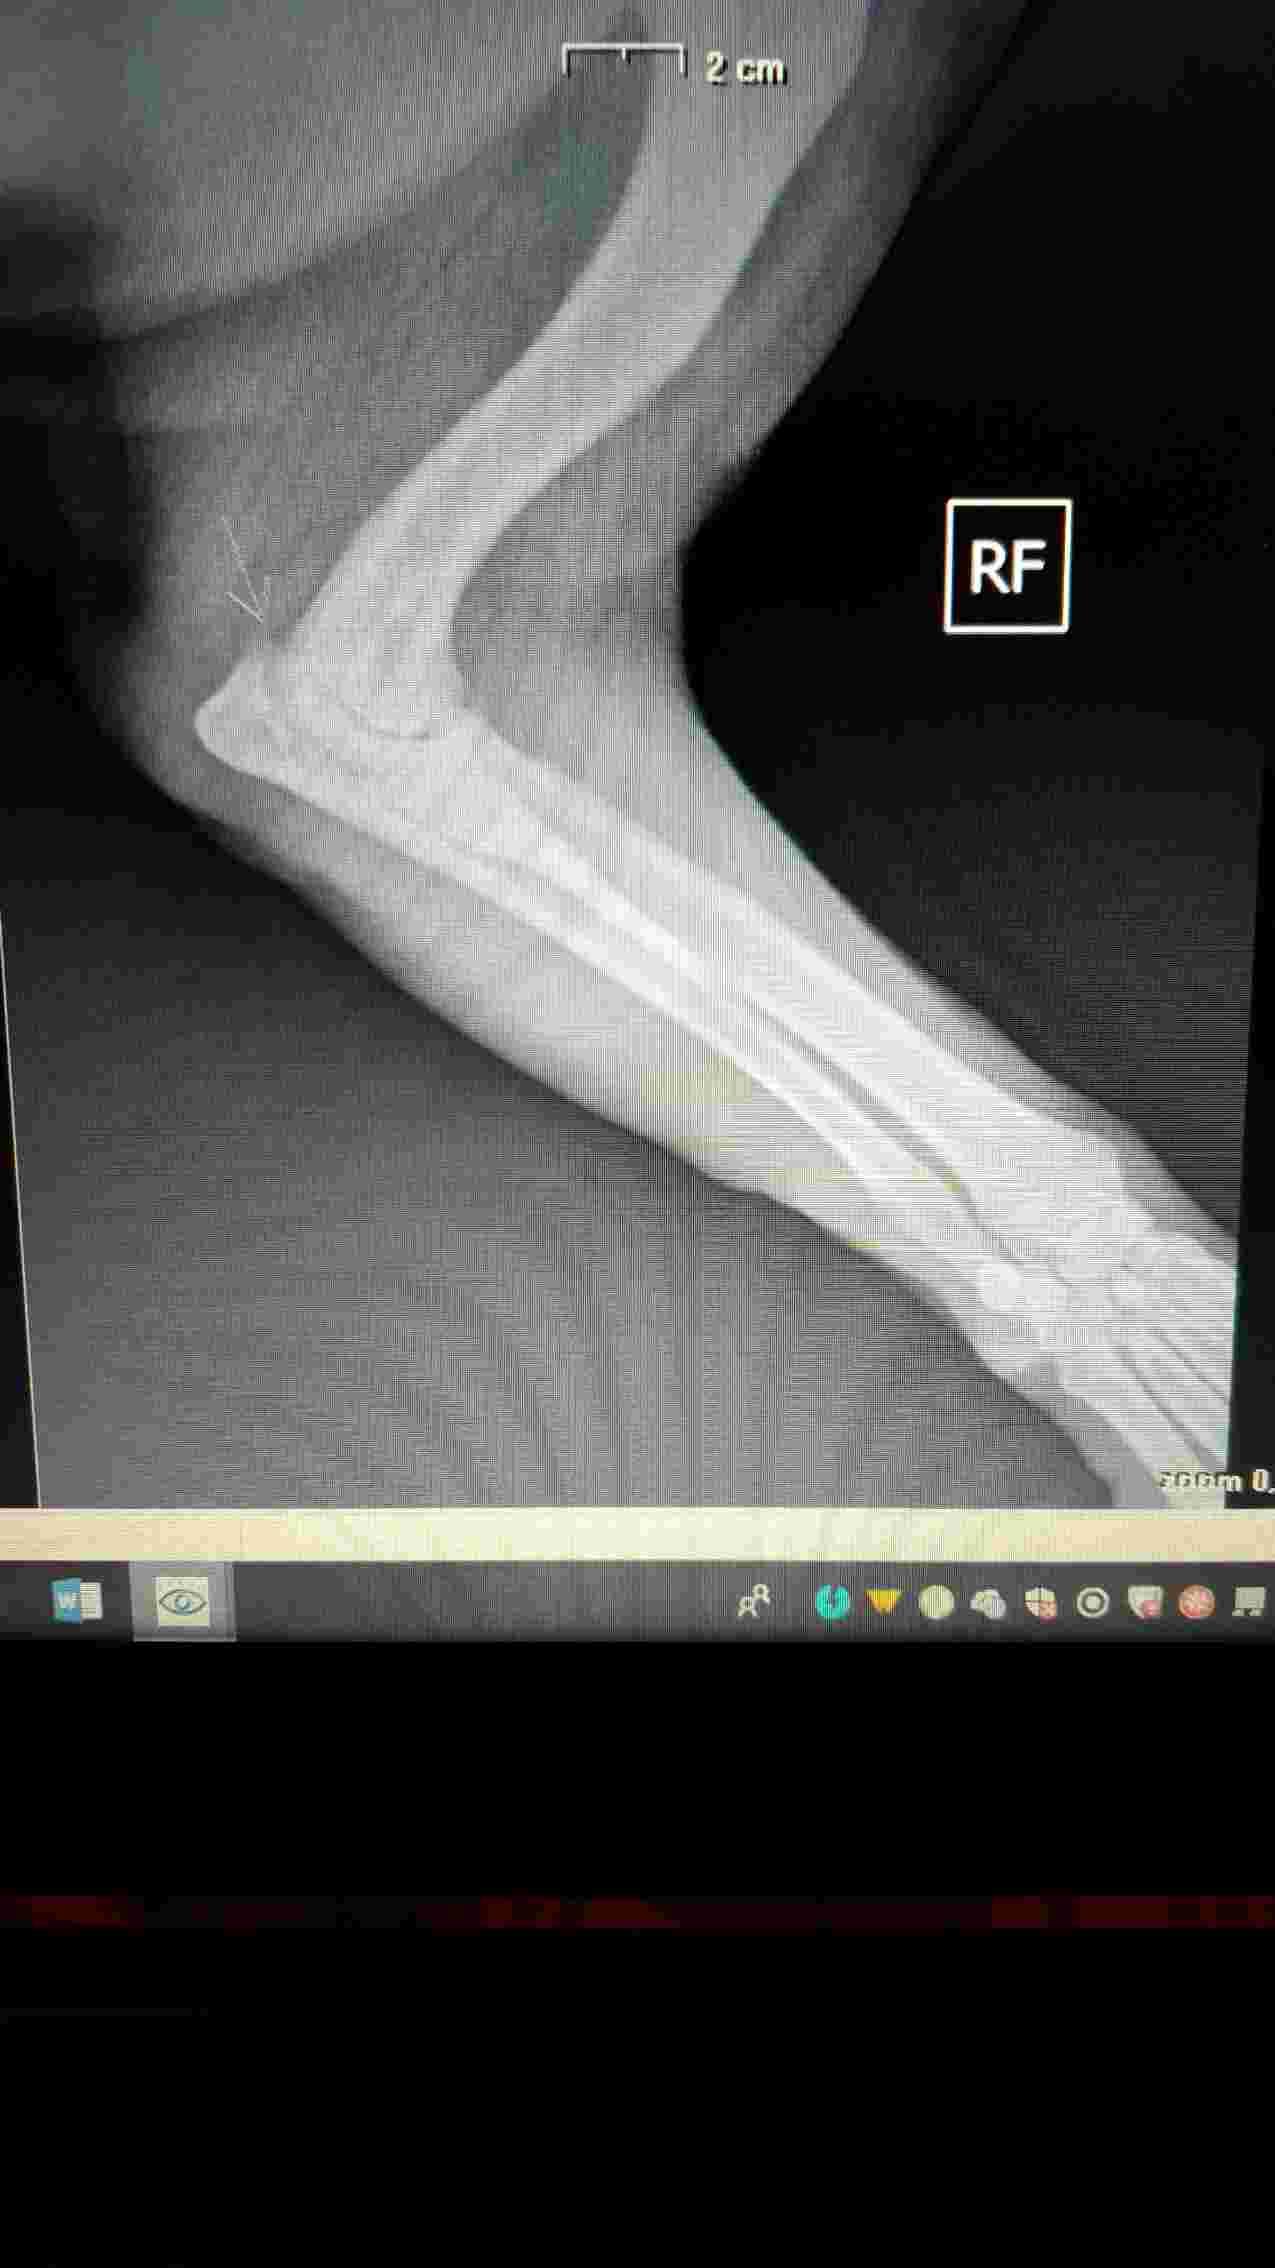

My chow chow is limping and feels some pain in right front elbow. The vet says that could be an elbow dysplasia. Any observation from you? Thank you !! P.s. He's 4 y and 7 mo old.

I do see some abnormal opacity in the elbow joint where the arrow is, so I would have to agree with your vet here. It is not possible to zoom in on x-rays that are copied here however, so its best to get a copy of the x-rays on a CD and then having them reviewed by a 2nd opinion doctor that way. Or you can ask your vet to send these to a radiologist who is well trained on picking up on small details that the untrained eye can miss. Another option is to treat medically for a minimum of 2 weeks, and if there is no improvement, then you know that is not just a muscle sprain or mild injury, and that elbow dysplasia is more likely the underlying cause. Doing a process of elimination, while still treating the pets pain, is a common thing that owners do when they are looking for a more conservative approach. If this is indeed elbow dysplasia, then I would recommend a referral to an orthopedic specialist if you want to pursue treatment. Treatment for this condition is often surgery. Poor guy. I hope that you can get him some relief soon. Best wishes and take care!